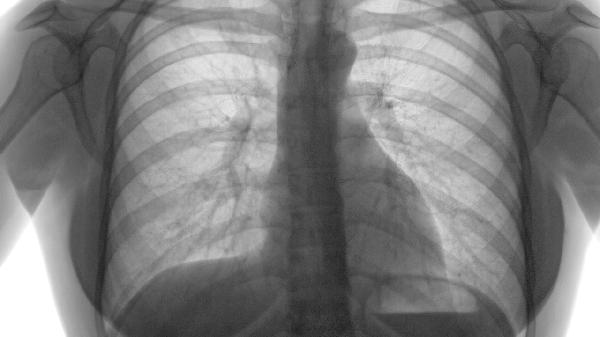

二氧化碳分压升高引发呼吸性酸中毒,血管通透性增加导致组织间隙液体积聚。动脉血气分析显示PaCO2>50mmHg时需考虑无创通气,严重者使用呼吸兴奋剂如尼可刹米注射液。

肺动脉高压加重右心负荷,颈静脉回流受阻引发颜面浮肿。超声心动图显示右心室扩大时,需联合利尿剂呋塞片20mg晨服、地高辛片强心治疗,限制每日钠盐摄入<3g。